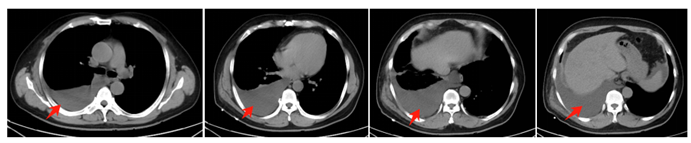

入院后完善相关实验室检查:生化检验报告:钾5.06mmol/L,钠129.8mmol/L,尿素氮22.06mmol/L,肌酐945.1umol/L,葡萄糖7.00mmol/L,肾小球滤过率7.1ml/min。血脂9项,肝功14项检验报告:高密度脂蛋白胆固醇1.13mmol/L,载脂蛋白A1 0.99g/L,总蛋白65.3g/l,白蛋白38.7g/L,谷丙转氨34U/L,谷草转氨酶38U/L。B型钠尿肽前体121.0ng/L,肌钙蛋白I <0.010ng/ml。血图分析1检验报告:血红蛋白116g/L,中性粒细胞68.6%,淋巴细胞百分比19.8%。糖化血红蛋白5.6%。尿液检查:尿蛋白(2+),尿隐血(2+),白细胞(-)。临检(粪便寄生虫检查,粪便检查2(常规+真菌),粪便隐血)检验报告:粪便隐血 弱阳性。胸部CT检查结果:右侧大量胸腔积液(图1)。

入院后予以胸腔穿刺抽液术,抽出淡黄色胸腔积液,胸水总蛋白3.4g/L,葡萄糖28.77mmol/L,LDH 29U/L,ADA 7.8U/L,胸水有核细胞53*10^6/L。腹水有核细胞24*10^6/L。腹腔注射亚甲蓝后引流出淡蓝色胸水,考虑胸腹瘘可能。遂于完善肝胆外科及胸外科会诊,后全身麻醉下行腹腔镜下膈肌修补术+腹腔探查术,取脐上3cm横行切口、脐上5cm处腹直肌左侧、剑突下3cm处、右侧肝肋缘下腋前线建立四个切口,术中探查右侧膈肌部位,肋膈角部边缘未见明显破孔,肝背侧缘的膈肌部位也未见明显破口,继续往肝脏顶缘膈肌探查时发现局部有细小裂纹,随呼吸局部有裂纹扩张,局部可见膈肌反常运动,考虑气腹后有轻微气胸发生,故局部考虑胸腹瘘发生,予以缝线沿裂纹部位间断及连续缝合,缝合后未见渗血及血肿形成,仔细探查其他右侧膈肌未见明显破口(图2)。